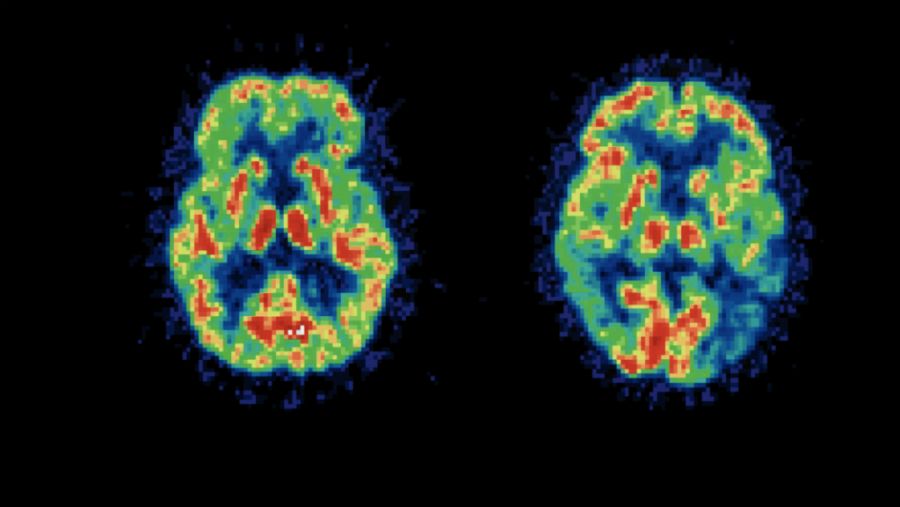

Escáner de un cerebro

Este tipo de demencia, diferente al Alzheimer, se da en gente más joven y es difícil de diagnosticar, ya que los tests de detección de alzhéimer no descubren la demencia frontotemporal.